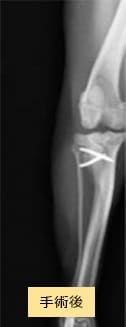

症例2

チワワ×マルチーズ(4歳10ヶ月齢、雌)グレードU〜V 外科手術

- 【初診時症状】

- 他院にて両後肢パテラグレードVと診断

手術を希望されて受診

- 【手術】

- 滑車溝形成術、脛骨粗面転位術、関節包縫縮を実施

- 【経過】

- 性格的にご自宅での安静が難しいため、術後2週間入院。術後4週間で屋内での運動制限を徐々に解除、8週間でお散歩の距離を少しずつ伸ばしていくも問題なし。

現在は制限なく生活